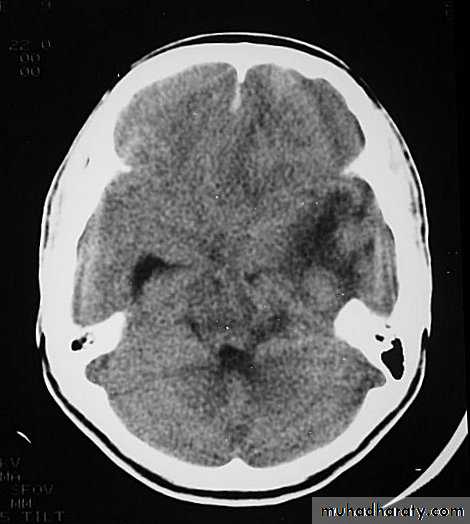

5. Hydrocephalus

a. Acutely due to obstruction of CSF outflow due to intraventricular blood.

b. Delayed post-traumatic communicating hydrocephalus due to impaired CSF reabsorption following traumatic subarachnoid haemorrhage

Intraventricular blood can lead to Hydrocephalus